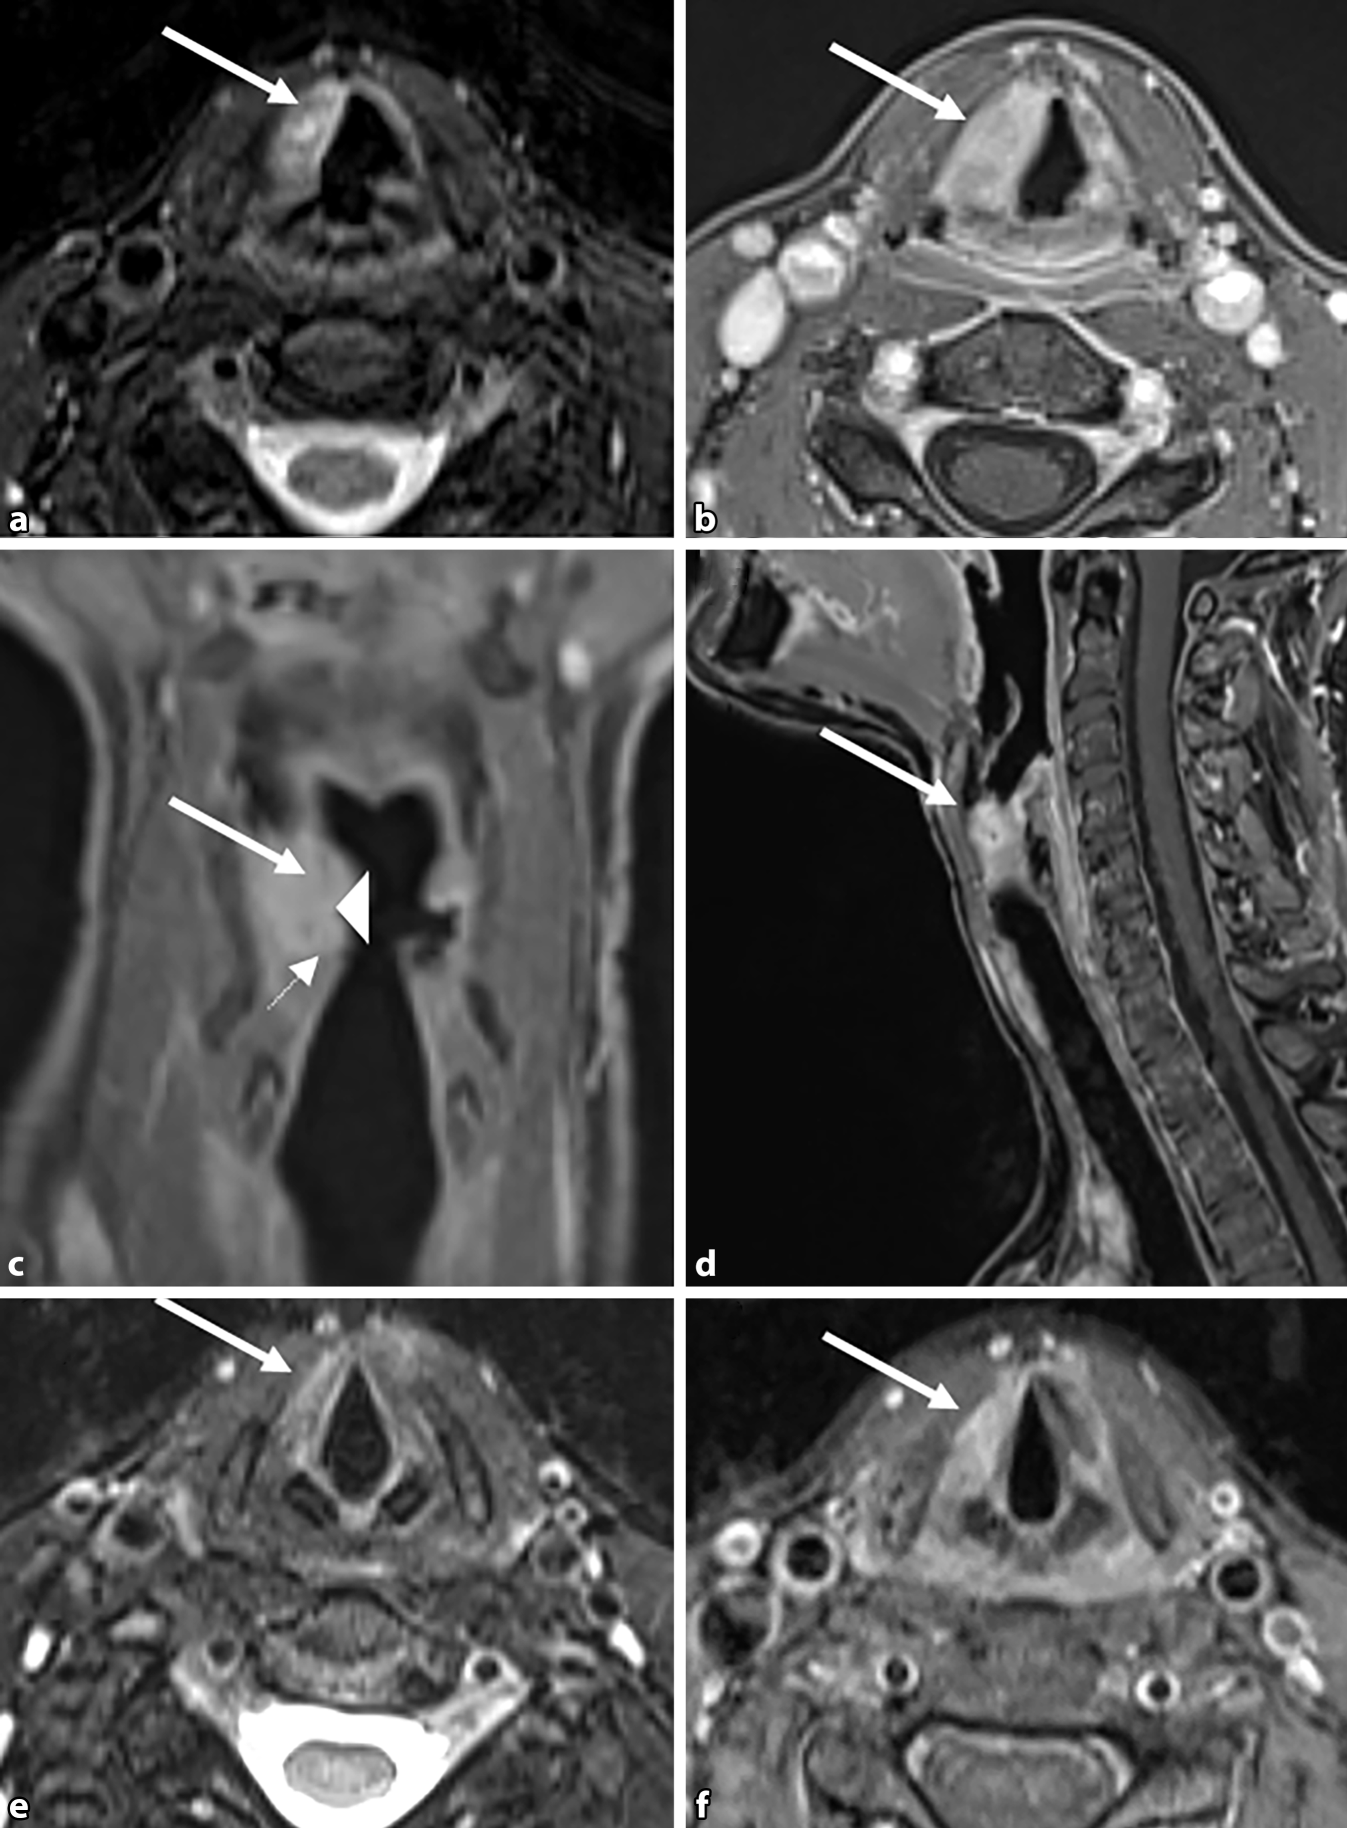

Aufgrund des unklaren Prozesses wurde eine Magnetresonanztomographie (MRT) des Hals durchgeführt, bei dem sich nach Gadolinium-Injektion eine T2w-hyperintense, kontrastmittelaufnehmende Veränderung in der Plica vestibularis (Abb. 2b–d, Pfeil) zeigte. Zeichen für Hyperzellularität ergaben sich hierbei radiologisch nicht.

Hals-MRT mit Fokus auf den Larynx: a Axiale T2-gewichtete Fatsat-Aufnahmen, b axial, c koronar, d sagittal mit T1w-Bildern nach Gadolinium-Injektion. Rechts eine supraglottische T2w-hyperintense, kontrastmittelaufnehmende Masse in der Plica vestibularis (Pfeil) und in geringerem Maße in der Plica vocalis (kleiner Pfeil), die die rechte Taschenfalte (Pfeilspitze) überlagert und die linke aryepiglottische Falte etwas nach medial verschiebt. In der postoperativen Nachuntersuchung (e axiale T2w-Fatsat-, f axiale T1w-Bilder nach Gadolinium-Gabe) ist die Masse nach der Debulking-Operation kleiner und weniger kontrastverstärkt

In der Diagnostik spielen neben der HNO-ärztlichen Untersuchung auch bildgebende Verfahren eine Rolle. Meist wird die laryngeale Amyloidose initial als tumorsuspekte Läsion in der direkten Laryngoskopie interpretiert [8]. Die Läsionen präsentieren sich häufig submukosal [11], teilweise auch mit zystischen Anteilen [7]. Die Amyloidmasse erscheint makroskopisch häufig gelblich-orange oder auch rötlich vom farblichen Aspekt ([10, 12, 13] Abb. 3e, Sternmarkierung). Bildgebende Verfahren wie CT und MRT stellen eine sinnvolle Ergänzung der Diagnostik dar, um das Ausmaß der Amyloidose zu bestimmen und mit den Symptomen der Patienten zu korrelieren. In der MRT ist die gut abgrenzbare, homogene, submuköse Läsion in der T2-Sequenz hyperintens sichtbar (Abb. 2a, Pfeilmarkierung). Eine CT könnte zusätzliche Informationen liefern, da hier in einigen Fällen Kalzifikationen nachgewiesen werden können [11]. Bei der vorliegenden Patientin wurde aufgrund von fehlender Konsequenz bei guter chirurgischer Resektabilität auf eine solche zusätzliche CT bewusst verzichtet. Eine definitive Diagnose kann dann aber nur durch histopathologische Aufarbeitung der Biopsie oder des Exzisionspräparats gesichert werden: